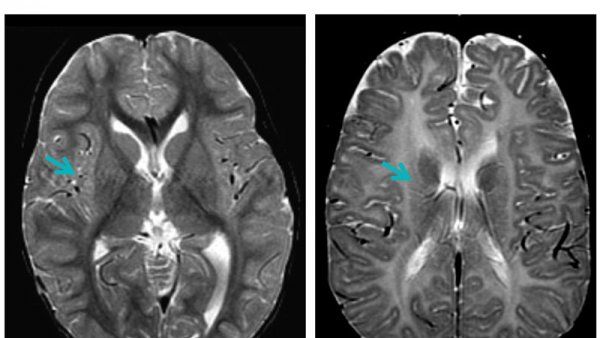

Research team has detected the immunological remnants of a common seasonal virus in spinal fluid from dozens of patients diagnosed with acute flaccid myelitis (AFM). The findings provide the clearest evidence to date that AFM is caused by an enterovirus (EV) that invades and impairs the central nervous system.